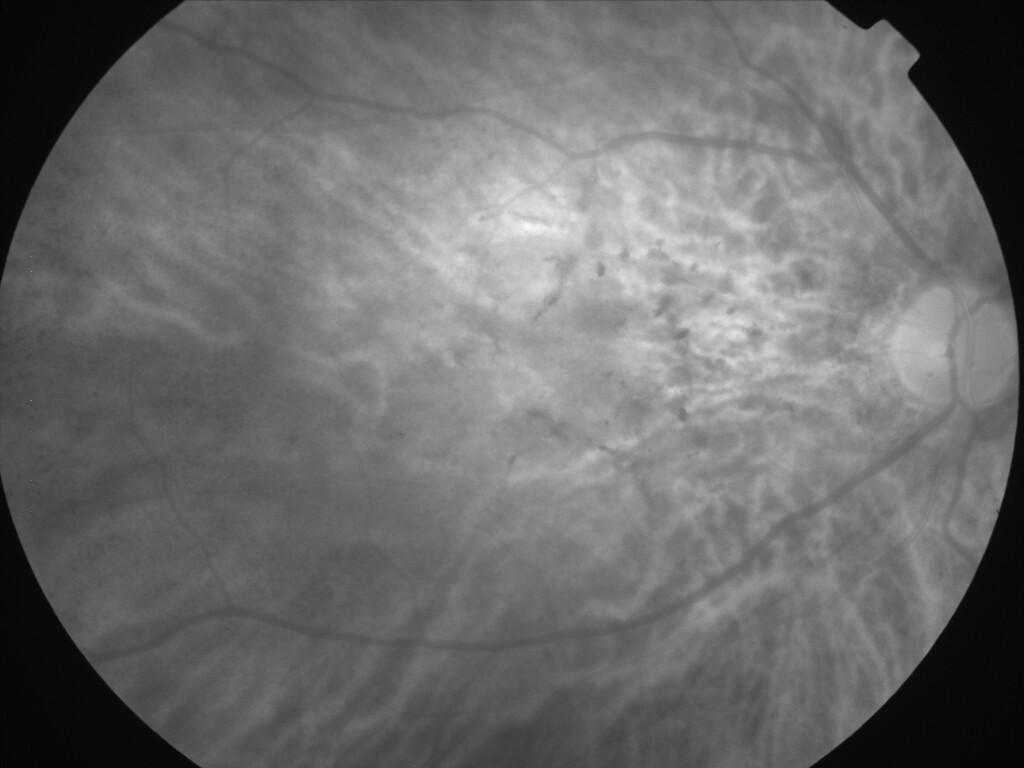

ASSOCIATION STRIES ANGIOIDES ET DYSROPHIE MACULAIRE RETICULEE

NEOVASCULARISATION